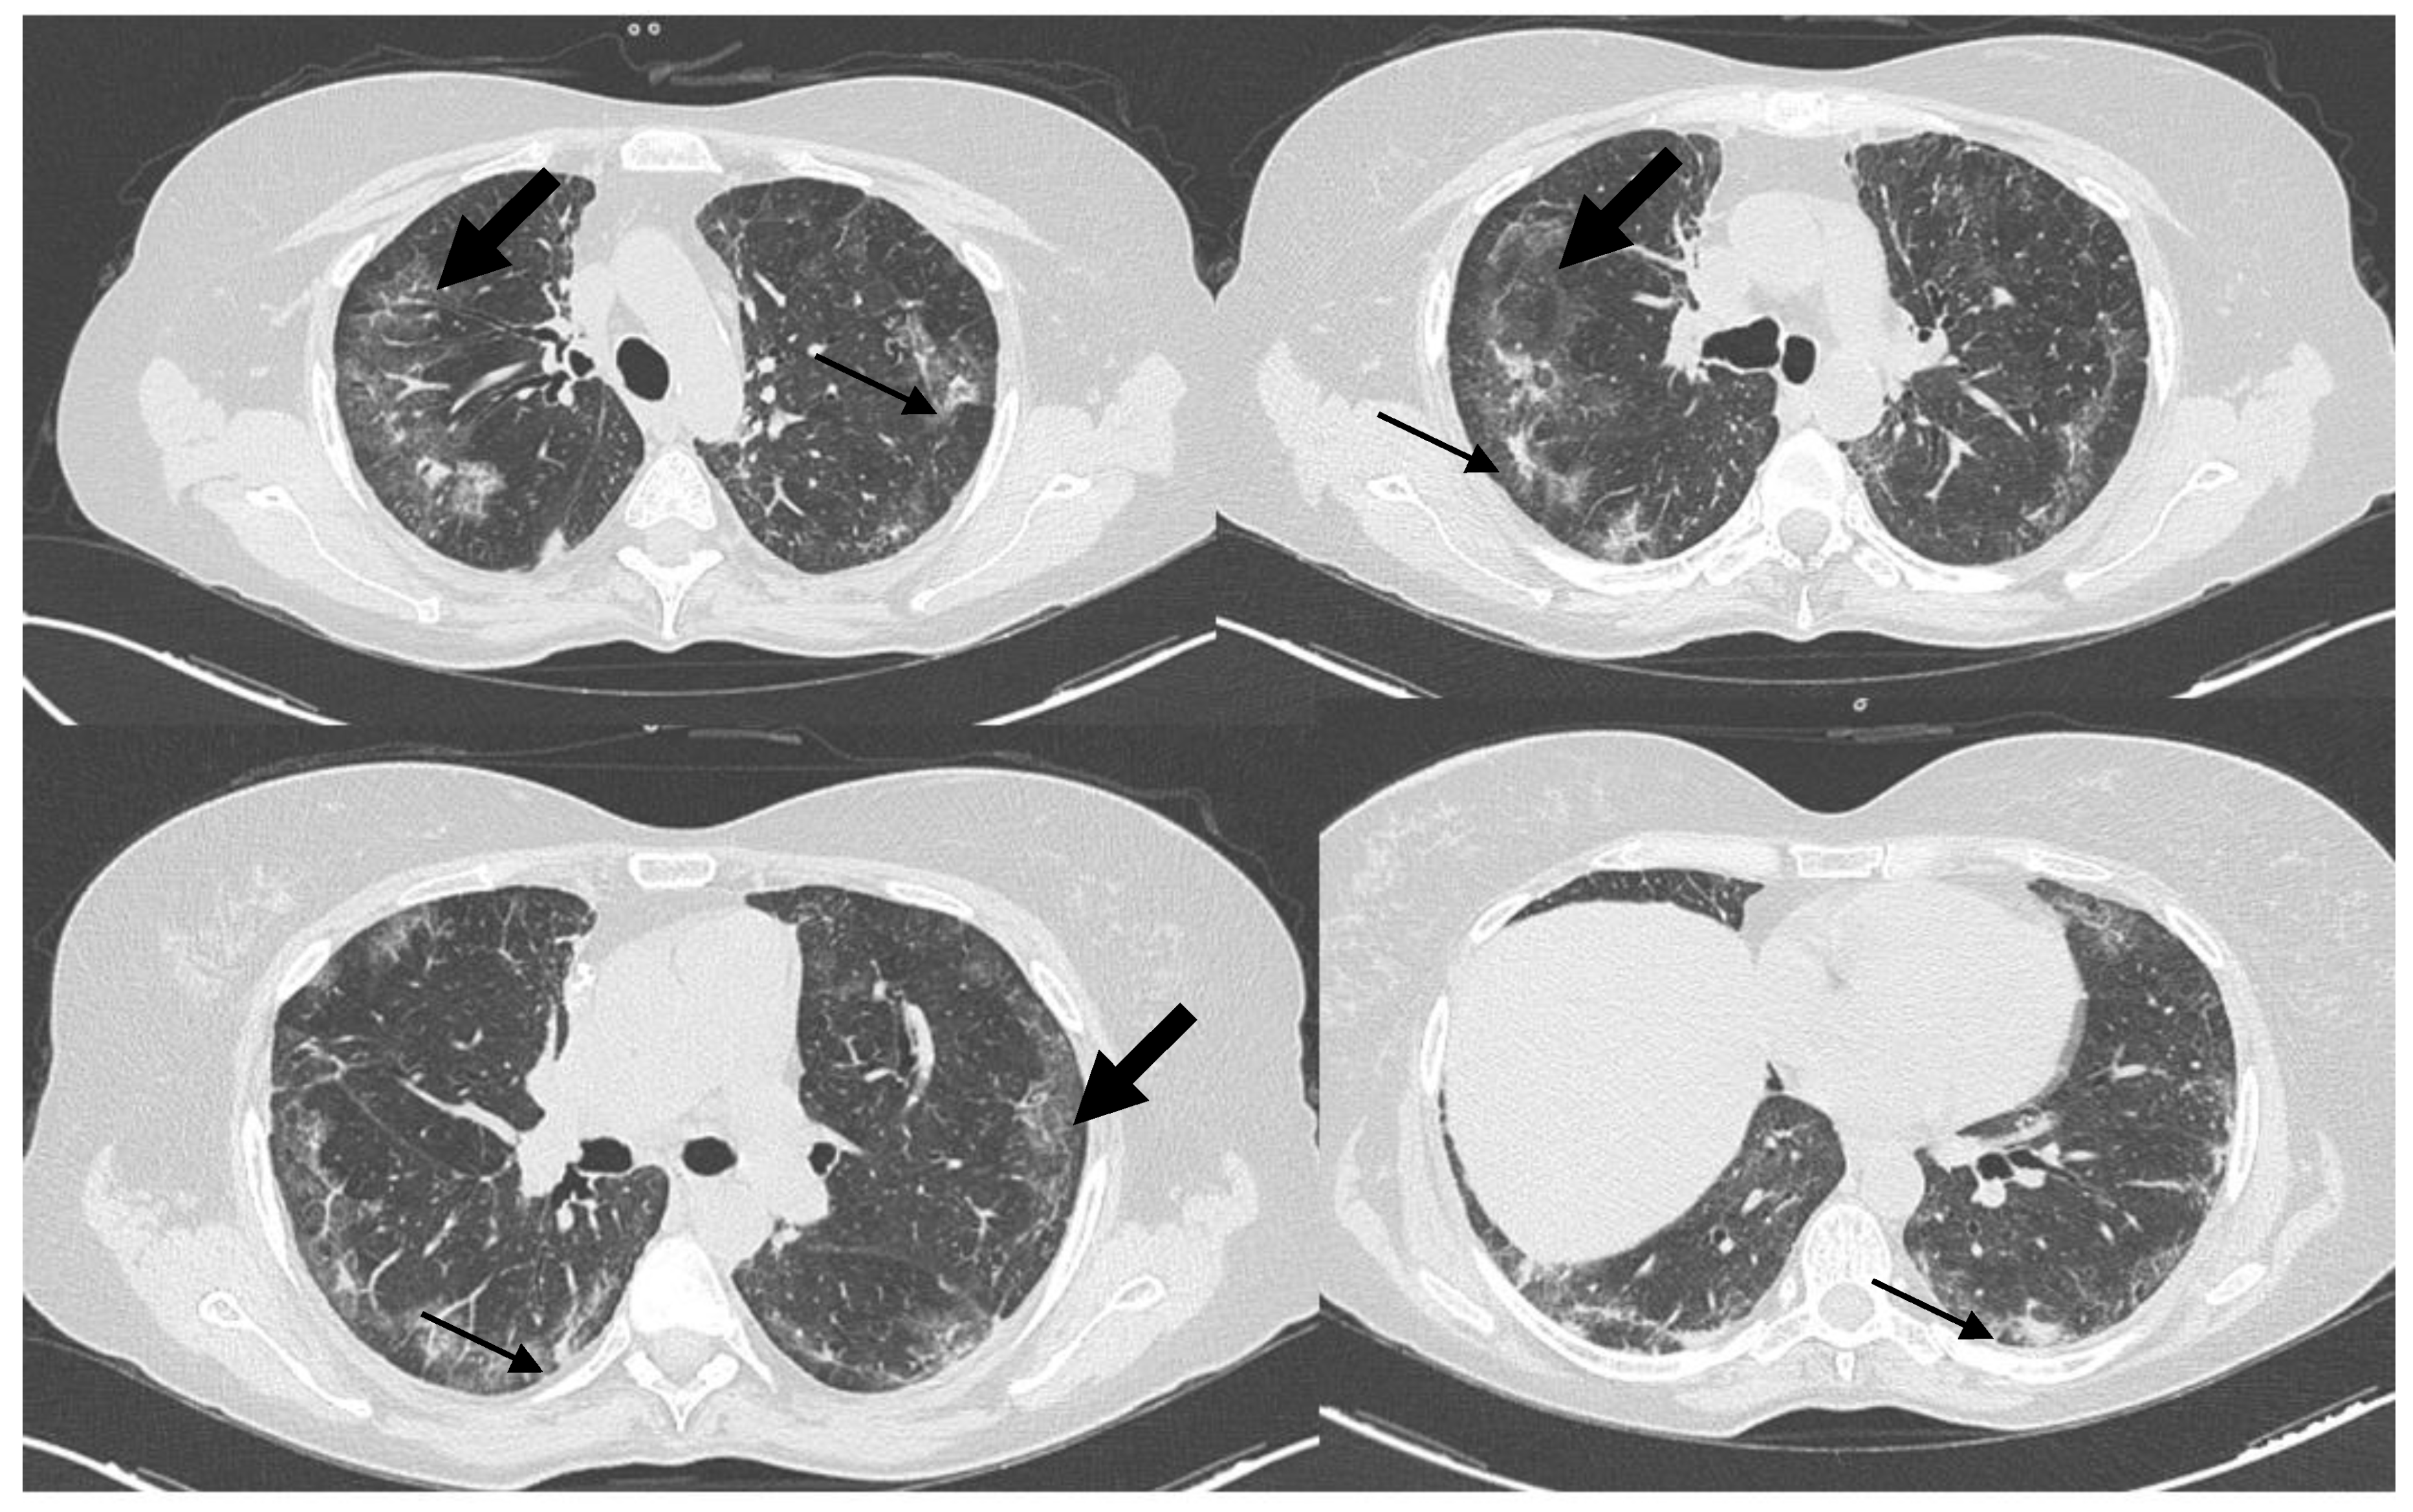

Watch the Mime Carefully! A Refractory Interstitial Lung Disease